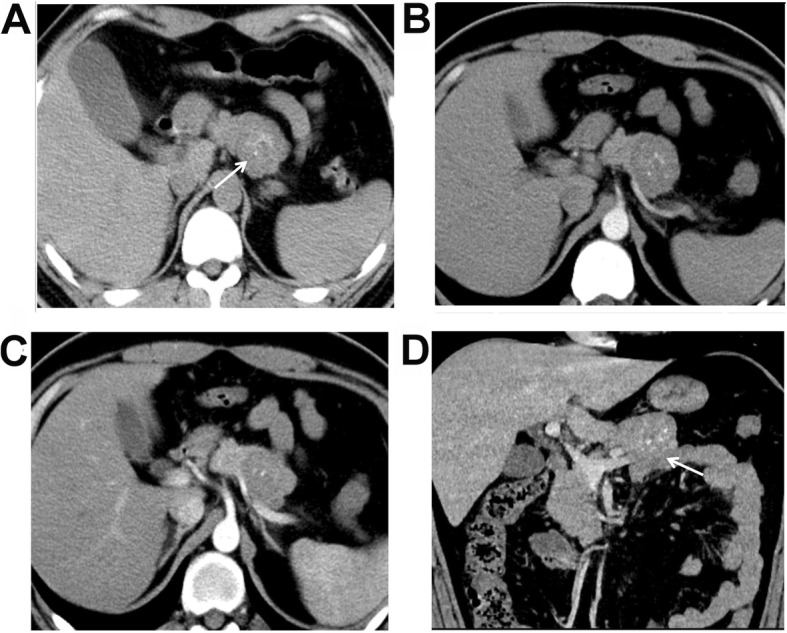

Fig. 1.

A 28-year-old male patient was found with pseudo-papillary neoplasm of pancreas (SPNP) at physical examinations. a An iso-density mass was found at the body of pancreas, and punctate calcifications were found in the mass (white arrow). b The enhancement in the arterial phase was not evident. c Persistent enhancement was found in the portal venous phase, with the enhancement increased evidently. d The boundaries of the tumor were clearly in the reconstructed coronal image (white arrow). No dilation of the pancreatic tube or bile duct was found, while atrophy of the pancreatic tail was shown